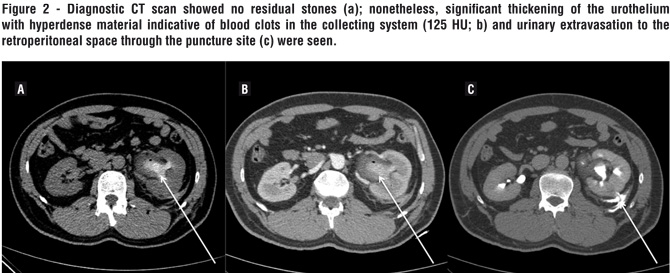

The patient underwent a percutaneous nephrolithotripsy (PCNL) in the complete supine position as previously described (3). A single puncture in the middle calyx provided access to the collecting system. Tract dilatation was performed with sequential dilators. An ultrasonic device was used to break and eliminate stone fragments. No significant bleeding occurred and a 6 Fr ureteral catheter was left in place. No nephrostomy tube or double J stent were used. On the first postoperative day, the patient developed severe left flank pain. His serum creatinine was 1.14 mg/dL and hemoglobin 12.8 g/dL. Diagnostic CT scan showed no residual stones (Figure-2a); nonetheless, significant thickening of the urothelium with hyperdense material indicative of blood clots in the collecting system (125 HU; Figure-2b) and urinary extravasation to the retroperitoneal space through the puncture site (Figure-2c) were seen.

Our main hypothesis is that bleeding from the collecting system with clot formation occurred due to the severe peripyelitis. Insufficient drainage due to clot obstruction and absence of a double J or nephrostomy tube led to fistula formation. Although based on a single case, an important lesson was learned: when preoperative CT reveals significant inflammation of the urothelium, adequate drainage of the collecting system is advised even when the surgery is uneventful and the patient becomes stone free. In most cases, peripyelitis’ diagnosis can only be made with the expertise of an experienced radiologist.